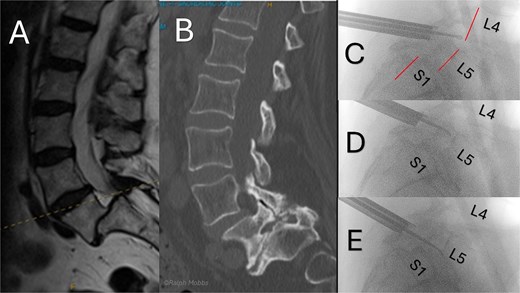

Standing radiographs and magnetic resonance imaging (MRI) demonstrated stable Grade-II L5/S1 degenerative spondylolisthesis with severe bilateral foraminal and lateral-recess stenosis compressing the exiting L5 and traversing S1 roots (Fig. 1). Computed tomography (CT) confirmed intact pars and severe facet arthropathy. Because open decompression/fusion was judged high risk due to significant comorbidities, uniportal full-endoscopic decompression alone under conscious sedation was offered.

Preoperative and intraoperative imaging of case 1. (A) Sagittal T2-weighted MRI demonstrating grade II degenerative spondylolisthesis at the L5/S1 level. (B) Axial T2-weighted MRI. (C–F) intraoperative fluoroscopic views illustrating the placement of the working channel and guidewire.

The operation was performed with patient in the prone position with free abdominal pressure. A skin incision was made positioned just lateral to the midline spinous process at the targeted lumbar interspace. Under fluoroscopic visualization, a series of dilators were advanced through the paraspinal muscles to the lamina, establishing a uniportal working channel (Elliquence, USA) for the endoscopic system with constant irrigation (Fig. 1). Hypertrophied ipsilateral ligamentum flavum and a portion of the ipsilateral facet joint were removed with radiofrequency probe, Kerrison rongeur and grasping forceps, preserving the majority of the facet joint on the approach side.